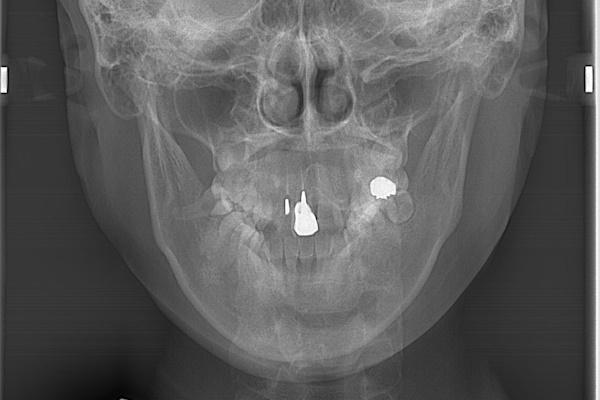

歯並びが悪いといっても様々なパターンがあり、患者様の症状によって治療法や期間が異なってきます。二子玉川駅前矯正歯科で矯正治療を行い、治療後に、症例提供のご協力いただいた患者様のお写真をお見せする事で、自分の治療のイメージをする事ができます。治療を終了した患者様のご協力のもと、代表的な歯並び別に分け、医療広告ガイドラインを守り、原因・症状・治療症例をまとめましたので、ご参考下さい。

■ 歯並び別分類